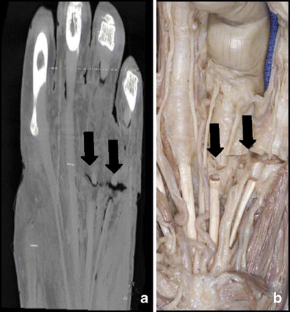

Flat-panel volume computed tomography (fpVCT) is a recent development in imaging. We discuss some of the musculoskeletal applications of a high-resolution flat-panel CT scanner. FpVCT has four main advantages over conventional multidetector computed tomography (MDCT): high-resolution imaging; volumetric coverage; dynamic imaging; omni-scanning. The overall effective dose of fpVCT is comparable to that of MDCT scanning. Although current fpVCT technology has higher spatial resolution, its contrast resolution is slightly lower than that of MDCT (5-10HU vs. 1-3HU respectively). We discuss the efficacy and potential utility of fpVCT in various applications related to musculoskeletal radiology and review some novel applications for pediatric bones, soft tissues, tumor perfusion, and imaging of tissue-engineered bone growth. We further discuss high-resolution CT and omni-scanning (combines fluoroscopic and tomographic imaging).